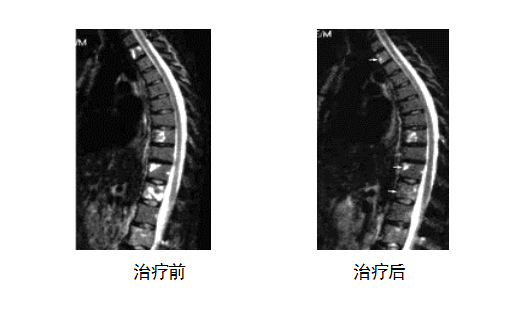

这是一例晚期合并骨转移的乳腺癌患者接受靶向性T细胞治疗前后的对比。接受治疗前,脊柱有多处转移灶,剧烈疼痛。

由免疫组化检测得知患者的肿瘤细胞表达Her2/neu,CEA和BA46这几个肿瘤相关抗原,是ACTL的攻击靶点,回输的T细胞可以精准消灭表达这些抗原的肿瘤细胞。经过四个月的治疗,脊柱转移灶明显减少,患者疼痛减轻,病情明显改善,生活质量显著提高。该患者已生存超过6年。